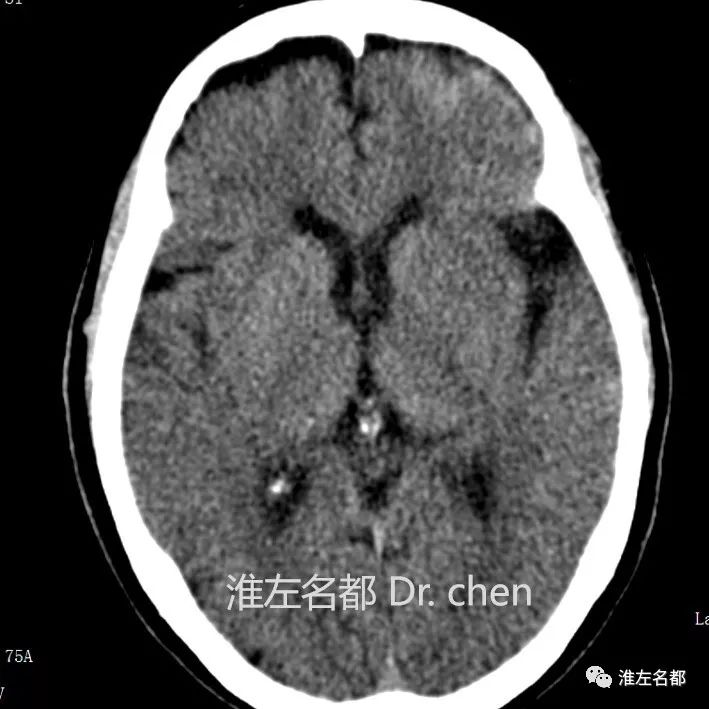

△CT平扫:左侧壳核前部稍低密度,边界模糊,

提示脑梗死。

△CT平扫:左侧侧裂池高密度影(红箭),提示蛛网膜下腔出血。